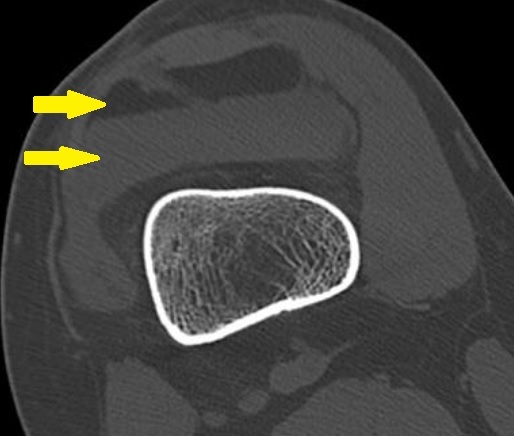

Identify

Lipohemarthrosis

In which joint type is effusion generally most easily identified?

knee